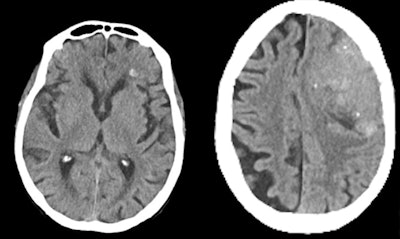

Oleaga and her team colleagues have trained an algorithm for detection of brain hemorrhage in acute stroke on noncontrast CT, with identification of the acute ischemic area and thrombus. The tool is far more reliable than human performance, the researchers found out.

(Left) True-positive brain hemorrhage in a patient with head trauma. (Right) False-positive hemorrhage in a patient with a left frontal calcified meningioma. Images courtesy of Prof. Dr. Laura Oleaga."We're not able to see the infarct at such an early stage, but the algorithm does," she said. "Such a tool can be useful in those centers who don't have the equipment to do advanced studies for stroke evaluation, to save time and make a decision to transfer the patient to centers for endovascular treatment."